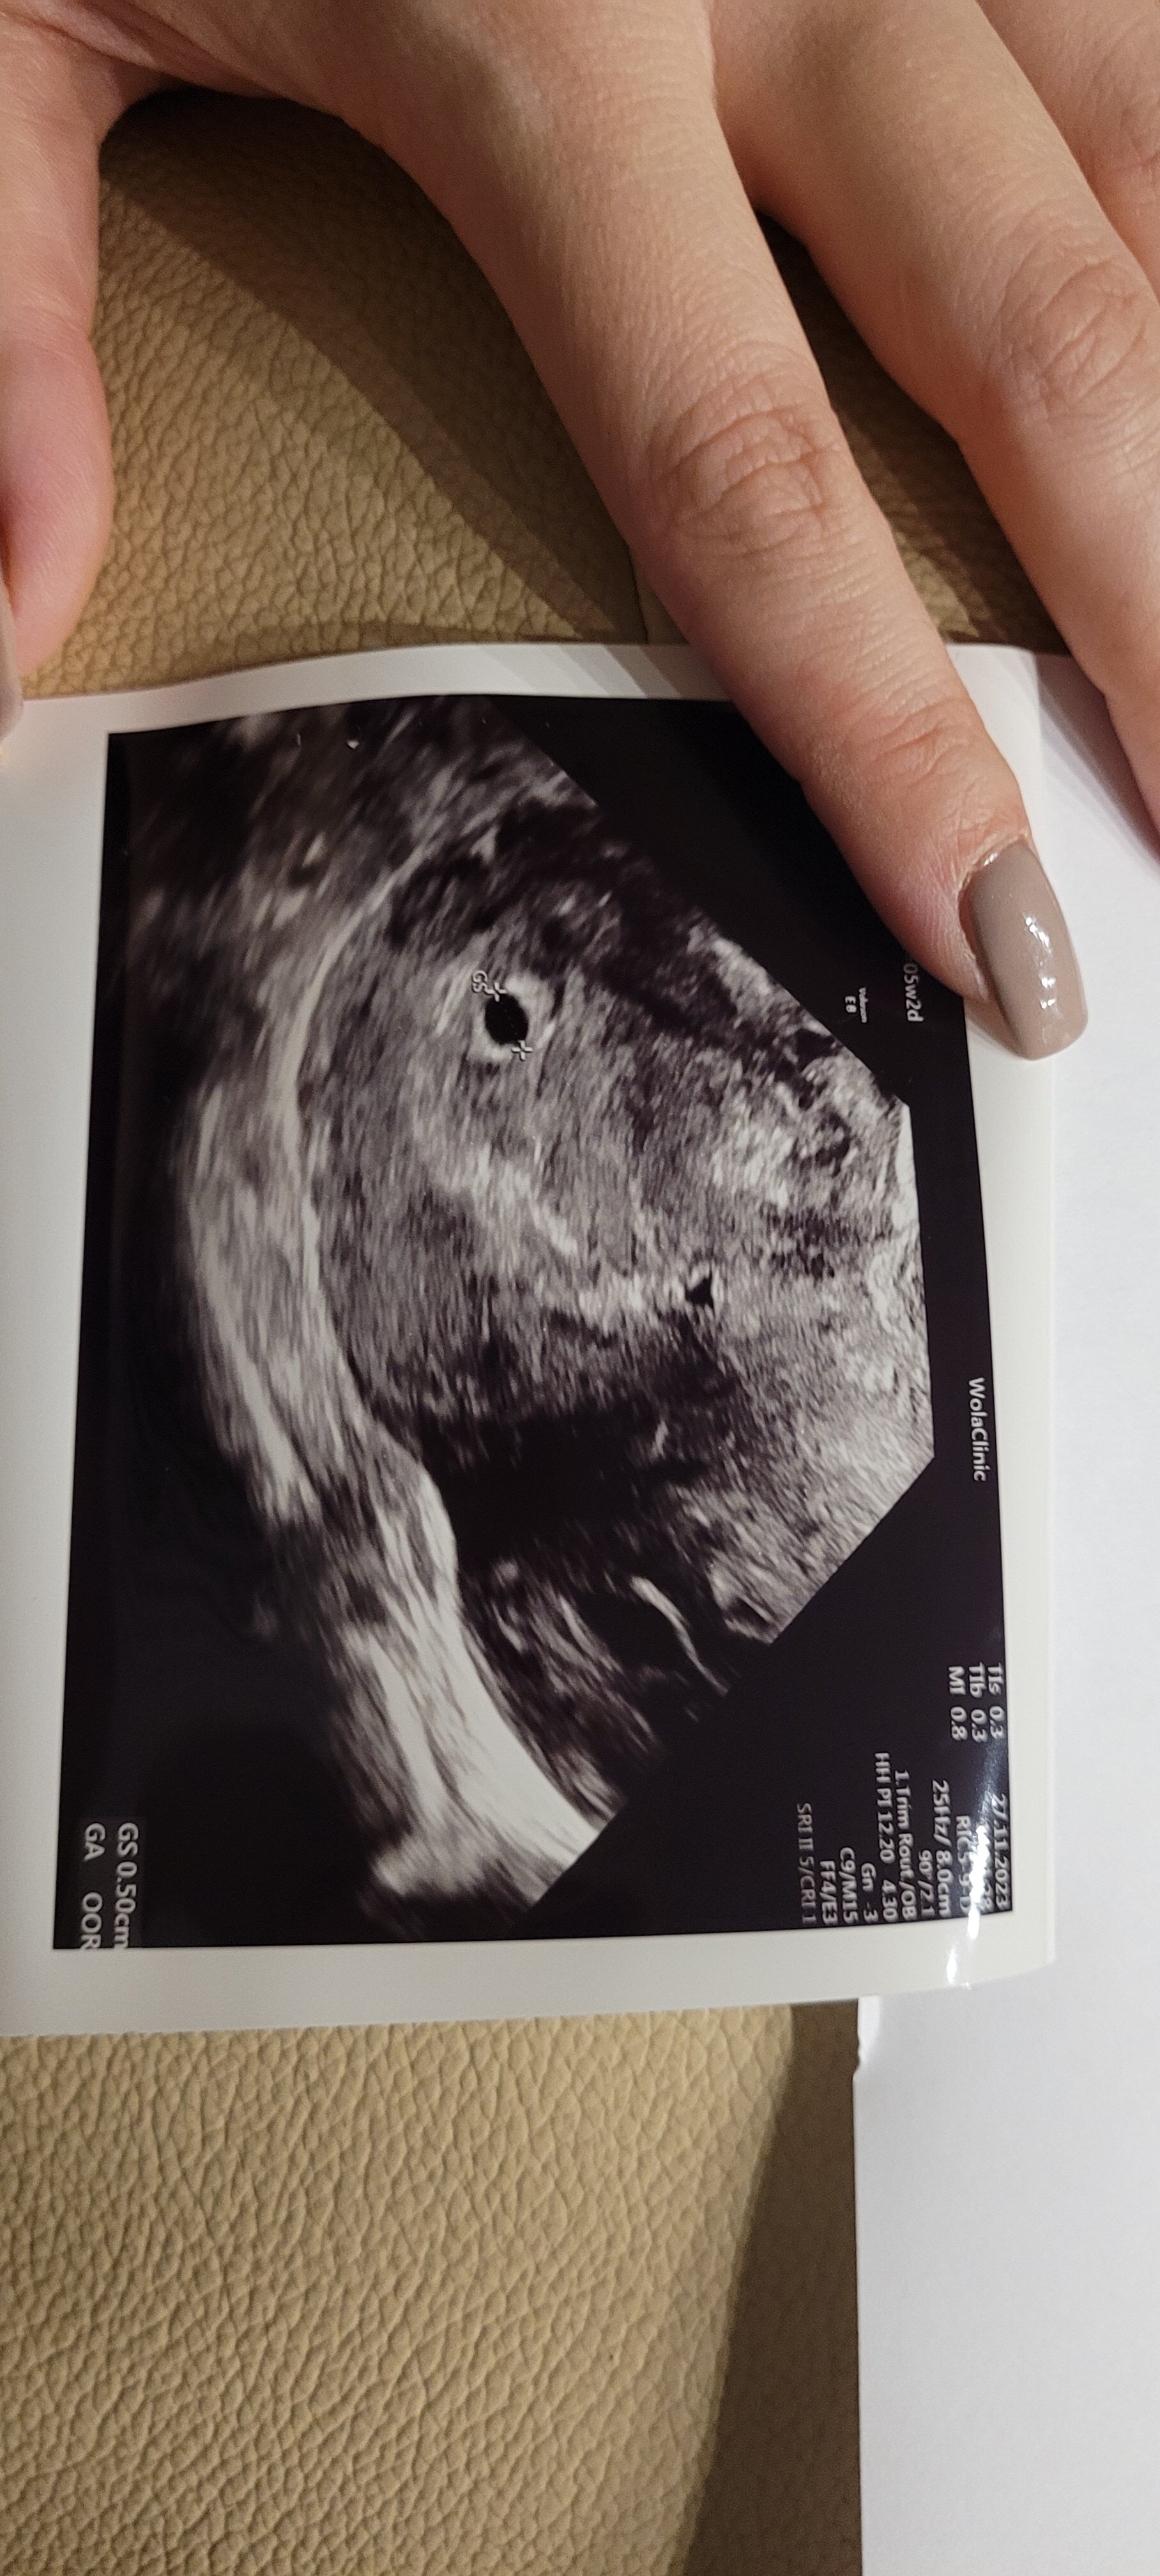

Natomiast wczoraj zestresował mnie lekarz z luxmedu... to było 5+4 i zobaczyl pęcherzyk... zapytam tylko czy widzi to co.powinien na tym etapie na co.on, że nie... bo to 6 tydzien i.powinien być już zarodek.

Wyszłam z przekonaniem, że pewnie skończy się jak.poprzednio... z tego stresu nie zapytalam .nawet czy jest pęcherzyk zóltkowy, chciałam tylko wyjsc i chciało mi sie ryczeć mimo, że ja z tym "twardych"... (mam zdjecie ale nie znam się) jestem zdołowana i chyba szukam wsparcia... by ktoś powiedział, że na tym etapie ciąży również nie ma jeszcze zarodka...